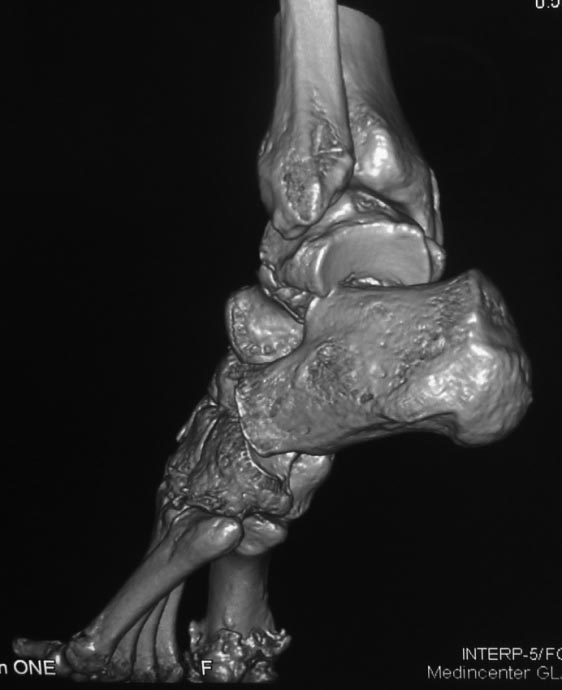

Во вложении похожий случай, оперированный 10 дней назад (с послеоперационными снимками). Для сравнения стрелками на двух рентгенограммах показан нависающий над пяточной костью вывихнутый фрагмент таранной кости. На компьютерной томограмме видно гораздо лучше. Так что о живом подтаранном суставе при сохраняющемся подвывихе говорить не приходится. Кстати, остеотомия внутренней лодыжки в такой ситуации - нормальный этап доступа, который должен планироваться до операции, а не быть следствием "тяжелой репозиции". Сейчас же, судя по плотности проксимального фрагмента, нужно исключать асептический некроз таранной кости и ее несращение. От этого будет зависеть тактика. Без КТ не обойтись. Во всяком случае, артродез голеностопного сустава при несросшейся разрушающейся таранной кости точно не будет правильным решением.